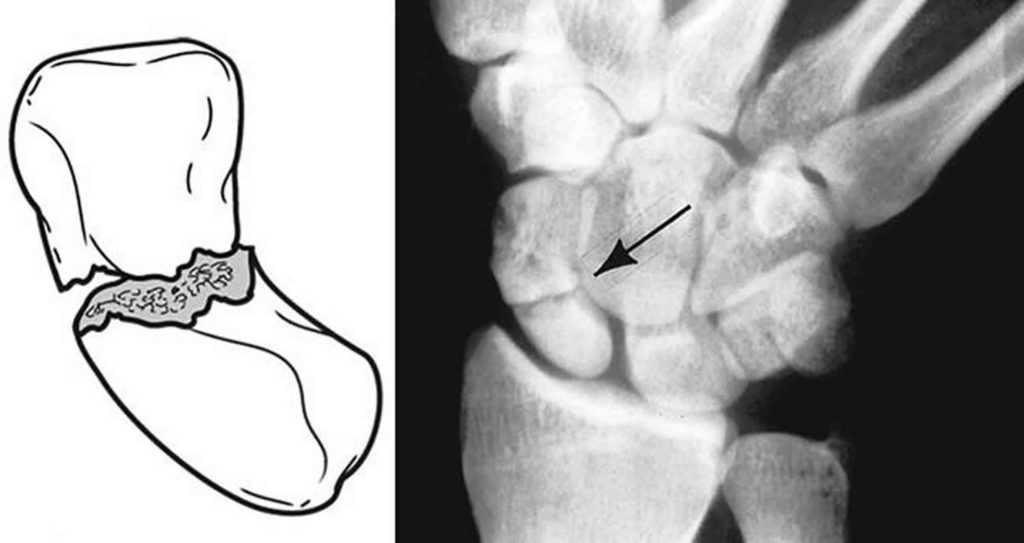

Scaphoid fracture Image Scaphoid Fracture Symptoms Numbness Scaphoid fractures are the most common carpal bone fracture, often occurring after a fall onto an outstretched hand. Swelling around the wrist area, particularly near the. T can lead to a condition called avascular necrosis, wher. Most people with a scaphoid fracture (which is the same as a broken wrist) will have pain and/or swelling along the thumb side of. Scaphoid Fracture Symptoms Numbness.